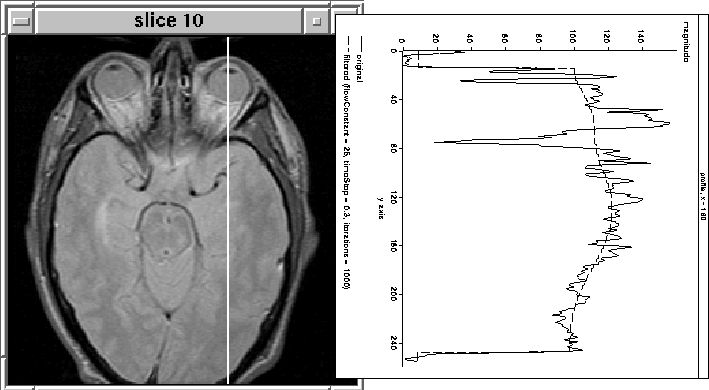

Figure 4.11 illustrates the result of filtering column 160 from another slice (10) using the same parameters as in Figure 4.10. gif Unfortunately, in this case the filter does not attenuate the intensity of the eyes.

Figure 4.11: 1D Diffusion. The filter has not attenuated the eye tissue as desired.